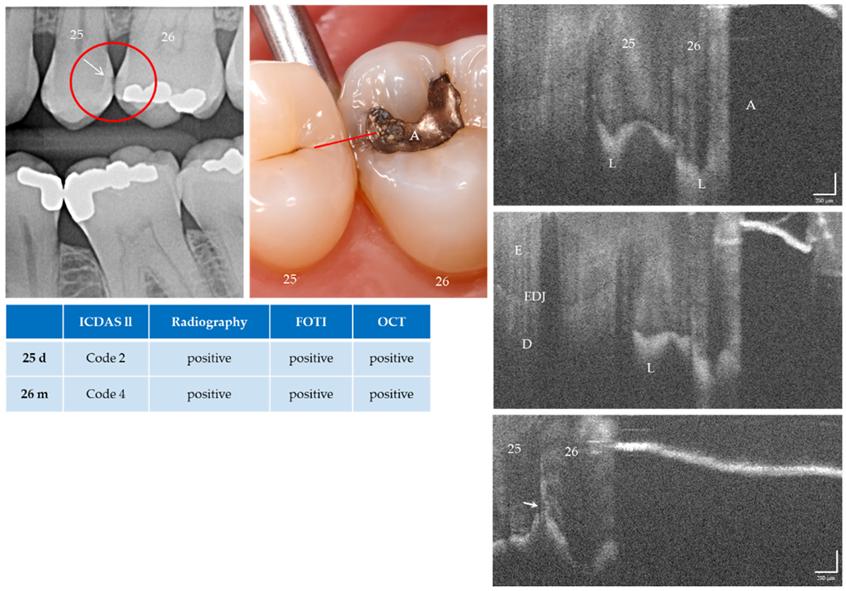

Figure 12.

Teeth 25 (d) and 26 (m). All methods diagnosed enamel caries lesions (L, arrow). On tooth 26 mesial the lesion was located next to an amalgam filling (A). The lower OCT image shows an irregularity in the enamel surface (arrow). An extensive lesion became visible by varying the angle of light incidence. Above the lesion the structures in the enamel are clearly visible. Whether the inclined signal in the surface of tooth 25 is a cavitation cannot be determined with certainty. Further OCT images taken orally and vestibularly did not provide clear additional information. Dentin involvement of the lesion is suspected, but an exact assessment is not possible due to local shadowing. As a result of focusing on deeper structures, the tooth surface has flipped in the OCT images. Enamel (E), dentin (D), enamel-dentin junction (EDJ). The vertical scales are related to the refractive index n = 1.0 (see remark in Figure 4).